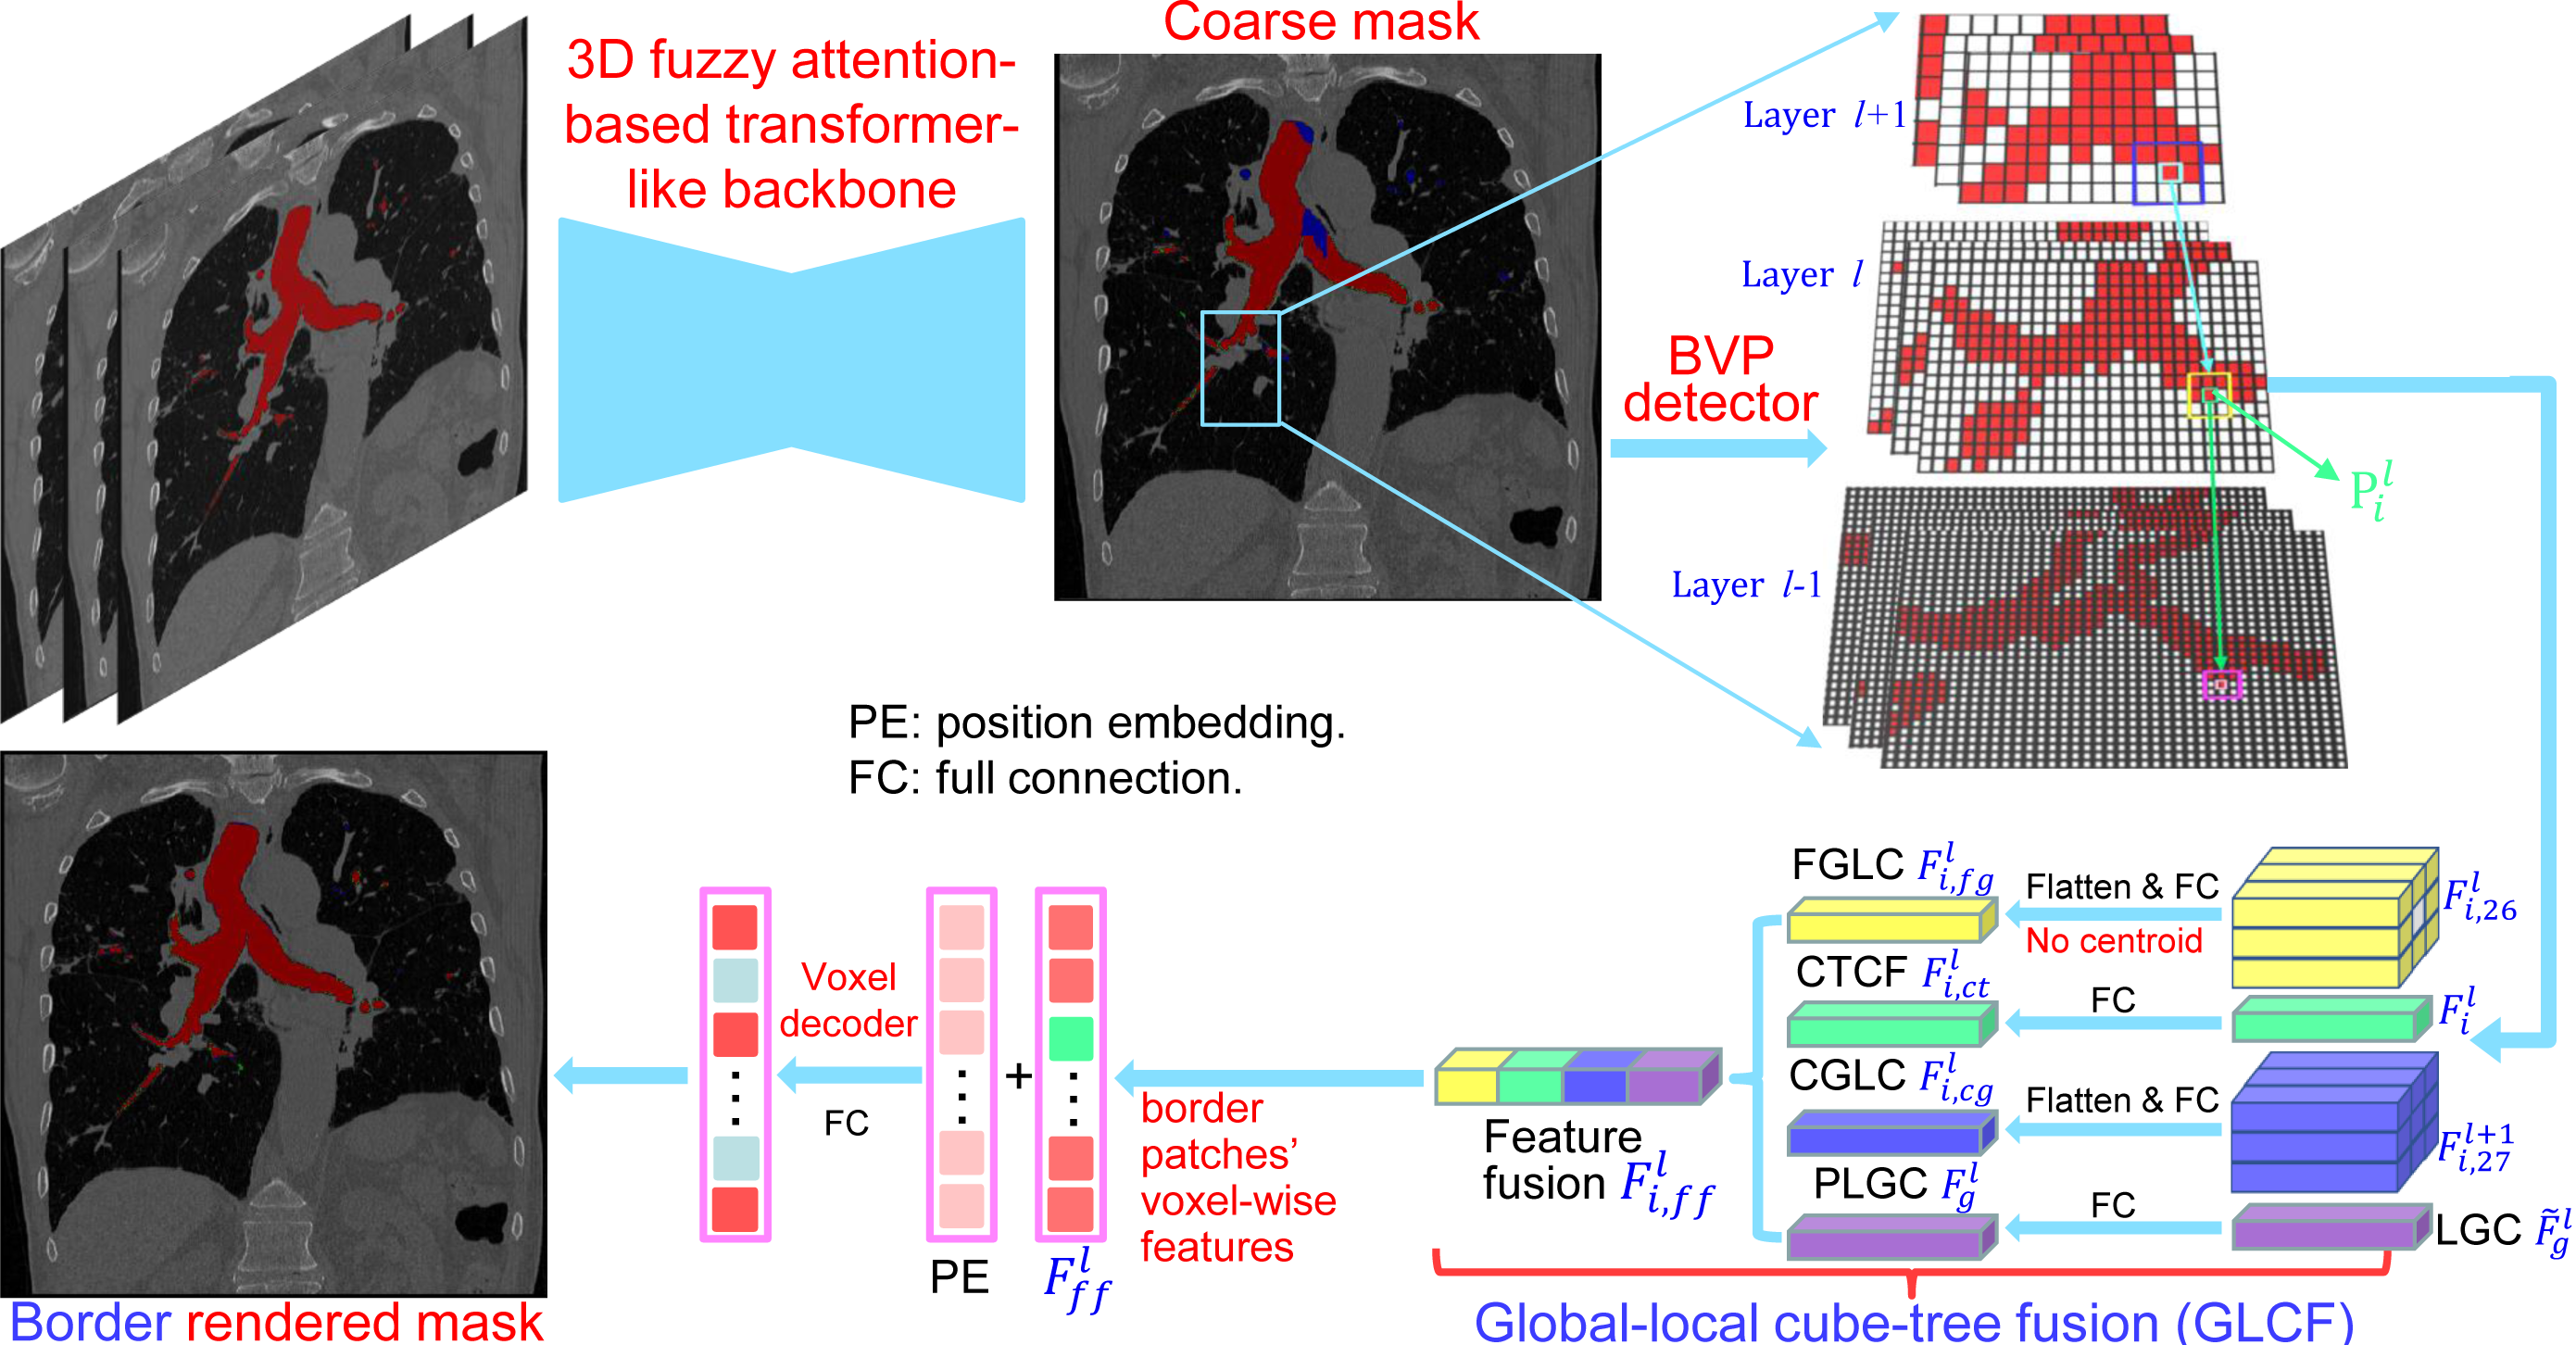

Automatic lung organ segmentation on CT images is crucial for lung disease diagnosis. However, the unlimited voxel values and class imbalance of lung organs can lead to false-negative/positive and leakage issues in advanced methods. Additionally, some slender lung organs are easily lost during the recycled down/up-sample procedure, e.g., bronchioles & arterioles, causing severe discontinuity issue. Inspired by these, this paper introduces an effective lung organ segmentation method called Fuzzy Attention-based Border Rendering (FABR) network. Since fuzzy logic can handle the uncertainty in feature extraction, hence the fusion of deep networks and fuzzy sets should be a viable solution for better performance. Meanwhile, unlike prior top-tier methods that operate on all regular dense points, our FABR depicts lung organ regions as cube-trees, focusing only on recycle-sampled border vulnerable points, rendering the severely discontinuous, false-negative/positive organ regions with a novel Global-Local Cube-tree Fusion (GLCF) module. All experimental results, on four challenging datasets of airway & artery, demonstrate that our method can achieve the favorable performance significantly.

To address these limitations in this paper, we propose an effective lung organ segmentation method called FABR. Unlike prior approaches, the method FABR fuses fuzzy sets and deep network to diminish the uncertainty in feature representations, decouples and depicts medical image regions as cube-trees, specifically targeting the border vulnerable points illustrated in Fig. 2. To address the challenges of severe discontinuity and false-negative/positive bronchioles and arterioles, we propose one innovative module of global-local cube-tree fusion, which fuses the learnable global embedding and local lung organ features.

The overview of our method FABR is detailed in Fig. 2. It mainly includes two modules, i.e., fuzzy attention-based transformer-like 3D U-shaped backbone and Global-Local Cube-tree Fusion (GLCF) module. The fuzzy attention-based transformer-like backbone is inspired by the well-known ConvNeXt [20] and detailed in Fig. 3, which includes a preliminary stem, sequential transformer-like regular/down/up-sample convolution blocks, a bottleneck and four efficient fuzzy attention modules, where each convolution block is constructed by applying a large kernel of 3D separable depth-wise convolution/deconvolution, group-normalization, transformer-like architecture (i.e., embedding 4 expansion/compression convolution layers like FFN module of transformer in our Fuzzy attention module) and GELU activation layer. The corresponding layers of the same scale between the encoder and decoder are linked by the efficient fuzzy attention layer. Besides, each-scale stage of the decoder is added by the 3D convolution and activation layers to predict the preliminary coarse masks of lung organ segmentation. Then, unlike the prior top-tier methods that operate on all regular dense points of the coarse masks to render the raw prediction, the proposed GLCF module decouples and depicts the medical image regions as cube-trees, which only focuses on the recycle-sampled BVP, and renders the severe discontinuity as well as false-negative/positive bronchioles or arterioles. We now elaborate the insights within the proposed method FABR for each innovative module in the following subsections.

2.2 Global-Local Cube-tree Fusion

To the best of our knowledge, most mask render-based two-stage semantic segmentation methods [6, 21] operate equally on all dense points of the coarse masks to improve the final performance, which is unnecessary to focus much on the already correctly predicted points. As shown in Fig. 1 and according to our statistical error analysis, most very vulnerable points occur on the object border due to the information loss caused by down-sample operation in the encoding process, especially for the innumerable bronchioles or arterioles in the tree-like structures. Thus, we only focus on the border vulnerable points and propose the novel global-local cube-tree fusion module. Specifically, (1) we “recycle” the down-sample and up-sample operations to produce masks and , and evaluate the absolute difference of them in Fig. 1 to get the border vulnerable points for the -th layer; (2) as shown in the top-right side of Fig. 2, we build the cube-tree of the -th point by extracting the local contextual features of {26, 27}-neighbors of the {, +1}-th layers respectively, which are defined as the cube without and with centroid. For the last layer, it is of note that we extract the 27-neighbors’ local contextual features in the adjacent layer -1; (3) we flatten features in the spatial dimension and project them as well as centroid feature into three vectors , which are separately related to the fine grain, coarse grain local context information and cube-tree centroid feature; (4) global airway or artery features from the distribution of the whole dataset is also very important, hence, we introduce the learnable global features to yield the projected global features , where is the embedding dimension; (5) we fuse the four features into as follows:

where [0, 1] are the learnable coefficients to balance the importance of each feature; (6) we lastly add the feature to the relative position embedding features (retaining the topology information for inductive bias) for the voxel-wise decoding and refined prediction. Obviously, our proposed global-local cube-tree fusion module focuses merely on all border vulnerable points in Fig. 1(f) rather than all regular dense points in Fig. 1(c), which is more related to the lung organ regions. Experimental results demonstrate the efficacy of this design.